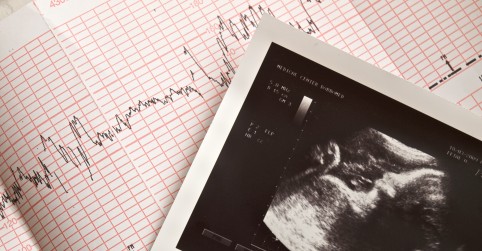

Trodimenzionalni Pregled Srca Ploda U Trudnoci